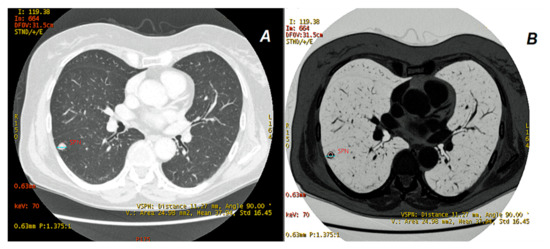

2. Materials and Methods

2.2. CT Scanning Parameters

2.3. Data Analyses

3. Results

3.1.2. Comparison of Iodine Concentration in IC Maps, Water Concentration (WC) and Radiation Absorption in Lung Tumors in AP and VP of DECT Examination